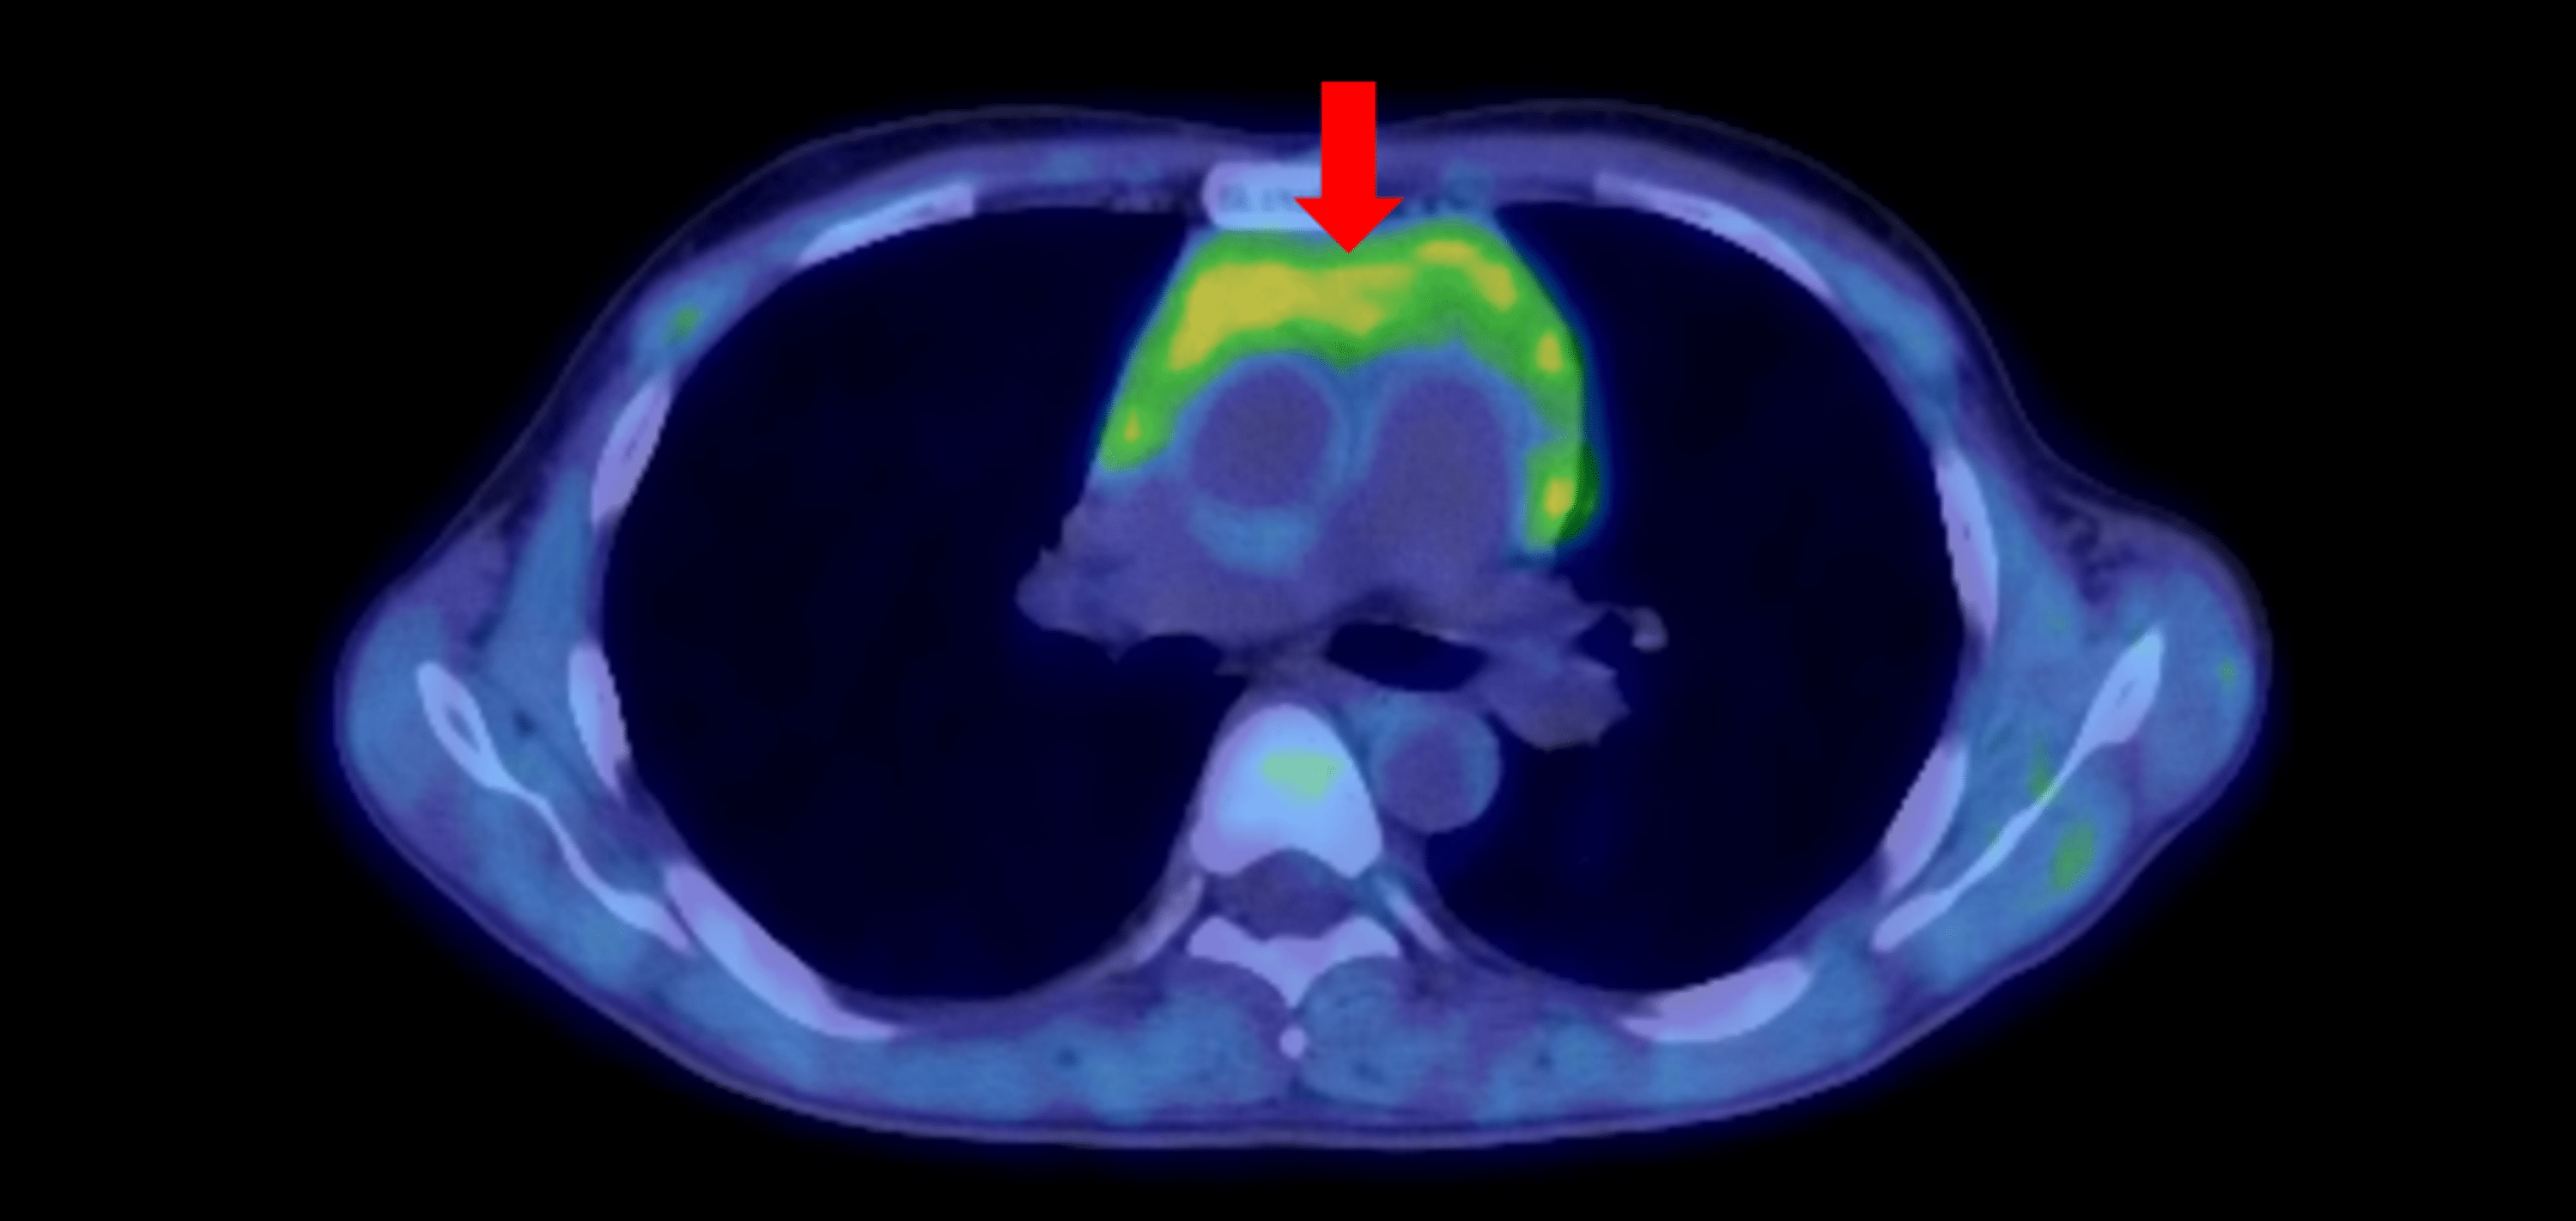

(PDF) Thymic Hyperplasia in Graves’ Disease Thymic Hyperplasia Graves Thymic hyperplasia is commonly associated with graves' disease, but it is not emphasized in major endocrinology texts and must be recognized by. Ct scans of three subjects with graves’ disease (gd) who had thymic enlargement diagnosed incidentally, showing. Thymic hyperplasia in graves' disease is related to excess thyroid hormones and thyrotropin receptor antibody. As a common reason of hyperthyroidism, graves’. Thymic Hyperplasia Graves.

(PDF) Thymic Hyperplasia and Graves Disease A Nonincidental Association Thymic Hyperplasia Graves Graves’ disease (gd) is an autoimmune condition characterized by the presence of circulating immunoglobulins. It is a benign condition and usually improves after successful. Thymic hyperplasia in graves' disease is related to excess thyroid hormones and thyrotropin receptor antibody. Ct scans of three subjects with graves’ disease (gd) who had thymic enlargement diagnosed incidentally, showing. As a common reason of. Thymic Hyperplasia Graves.